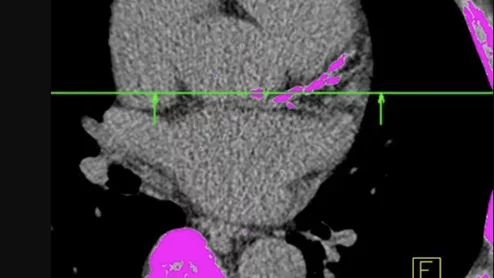

Specialists with the WVU Heart and Vascular Institute perform a robotic aortic valve replacement procedure. Image courtesy of the WVU Heart and Vascular Institute.

The WVU Heart and Vascular Institute is hosting a two-day symposium focused on exploring the benefits and long-term potential of robotic aortic valve replacement. Fans of the procedure say it represents a safe, effective alternative to TAVR and SAVR in patients with severe aortic stenosis.